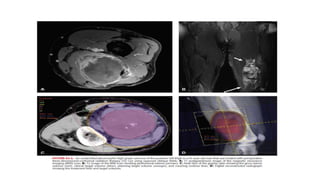

Target Volumes andTreatment Fields Preoperative Radiation Therapy: • Fusion of the diagnostic MRI and planning CT for optimal target definition is strongly encouraged. • GTV is defined as the gross tumor delineated by the T1 postgadolinium MRI. • Clinical target volume (CTV) is defined as the GTV plus 3-cm margins in the longitudinal directions and 1.5-cm margins radially. • PTV: CTV plus 5 to 10 mm

Postoperative Radiation Therapy •The CTV should encompass all the tissues handled during the surgery including the incision and any drain sites. (Postoperative changes seen on MRI help define the operative bed.) • An additional longitudinal margin of 2 to 4 cm and a radial margin of 1.5 to 2 cm is generally added to the operative bed to form the CTV. • The PTV is typically CTV plus 5 to 10 mm. • A second (and sometimes third) course field reduction is typically used in the postoperative setting. CTV margins for the reduced field(s) vary and can include about 2 cm on the operative bed or on the initial GTV. (Baldini et al. found no recurrences in 36 patients with resection margins ≥1 cm compared to an actuarial 10-year LR rate of 13% (4 of 38) for those with margins <1 cm.) Perez and Brady’s 6TH